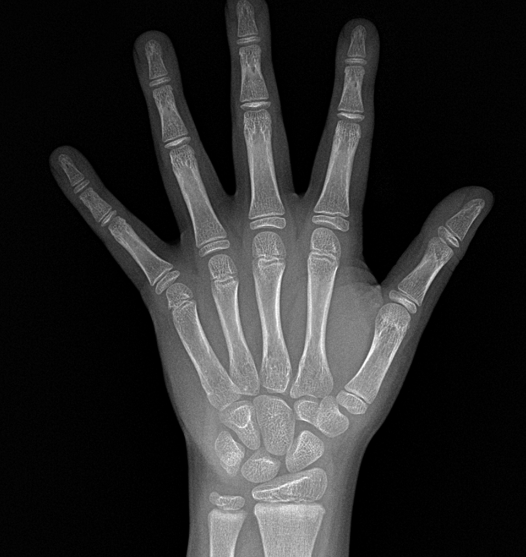

- 골연령 : 12세 3개월

진찰 소견상 사춘기 후반에 진입하였고 Tanner stage4 (초경, 음모) 였으며 골연령은 실제나이에 비해 1년9개월 증가되어있었습니다. 성성숙이 빠르게 진행되어 이미 사춘기 후반으로 진입한 전형적인 모습이었습니다.

사춘기 후반에 중요한 Risser sign 또한 stage3 에서 stage4로 넘어가는중으로 확인되었습니다. 그렇다는 얘기는 추후에 자랄수 있는 기간이 많이 남아있지 않다는 의미였습니다.

골연령 | 12세 3개월 | 12세 3개월 | 13세 | 13세 6개월 | 14세 |